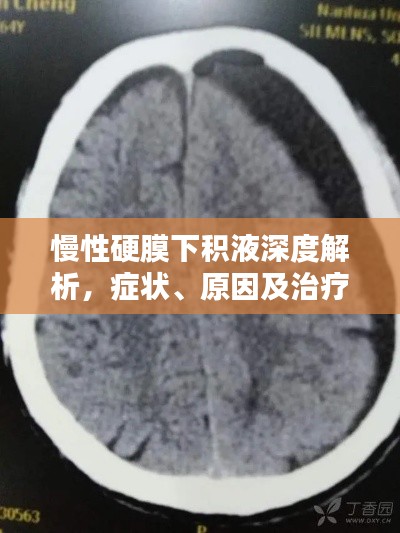

诊断与治疗

对于慢性硬膜下积液的诊断,通常需要进行头颅CT或MRI等影像学检查,治疗方法主要包括药物治疗和手术治疗,药物治疗主要是对症治疗,如使用脱水药物降低颅内压等,对于严重的慢性硬膜下积液,可能需要手术治疗以消除积液并恢复颅内压力平衡。